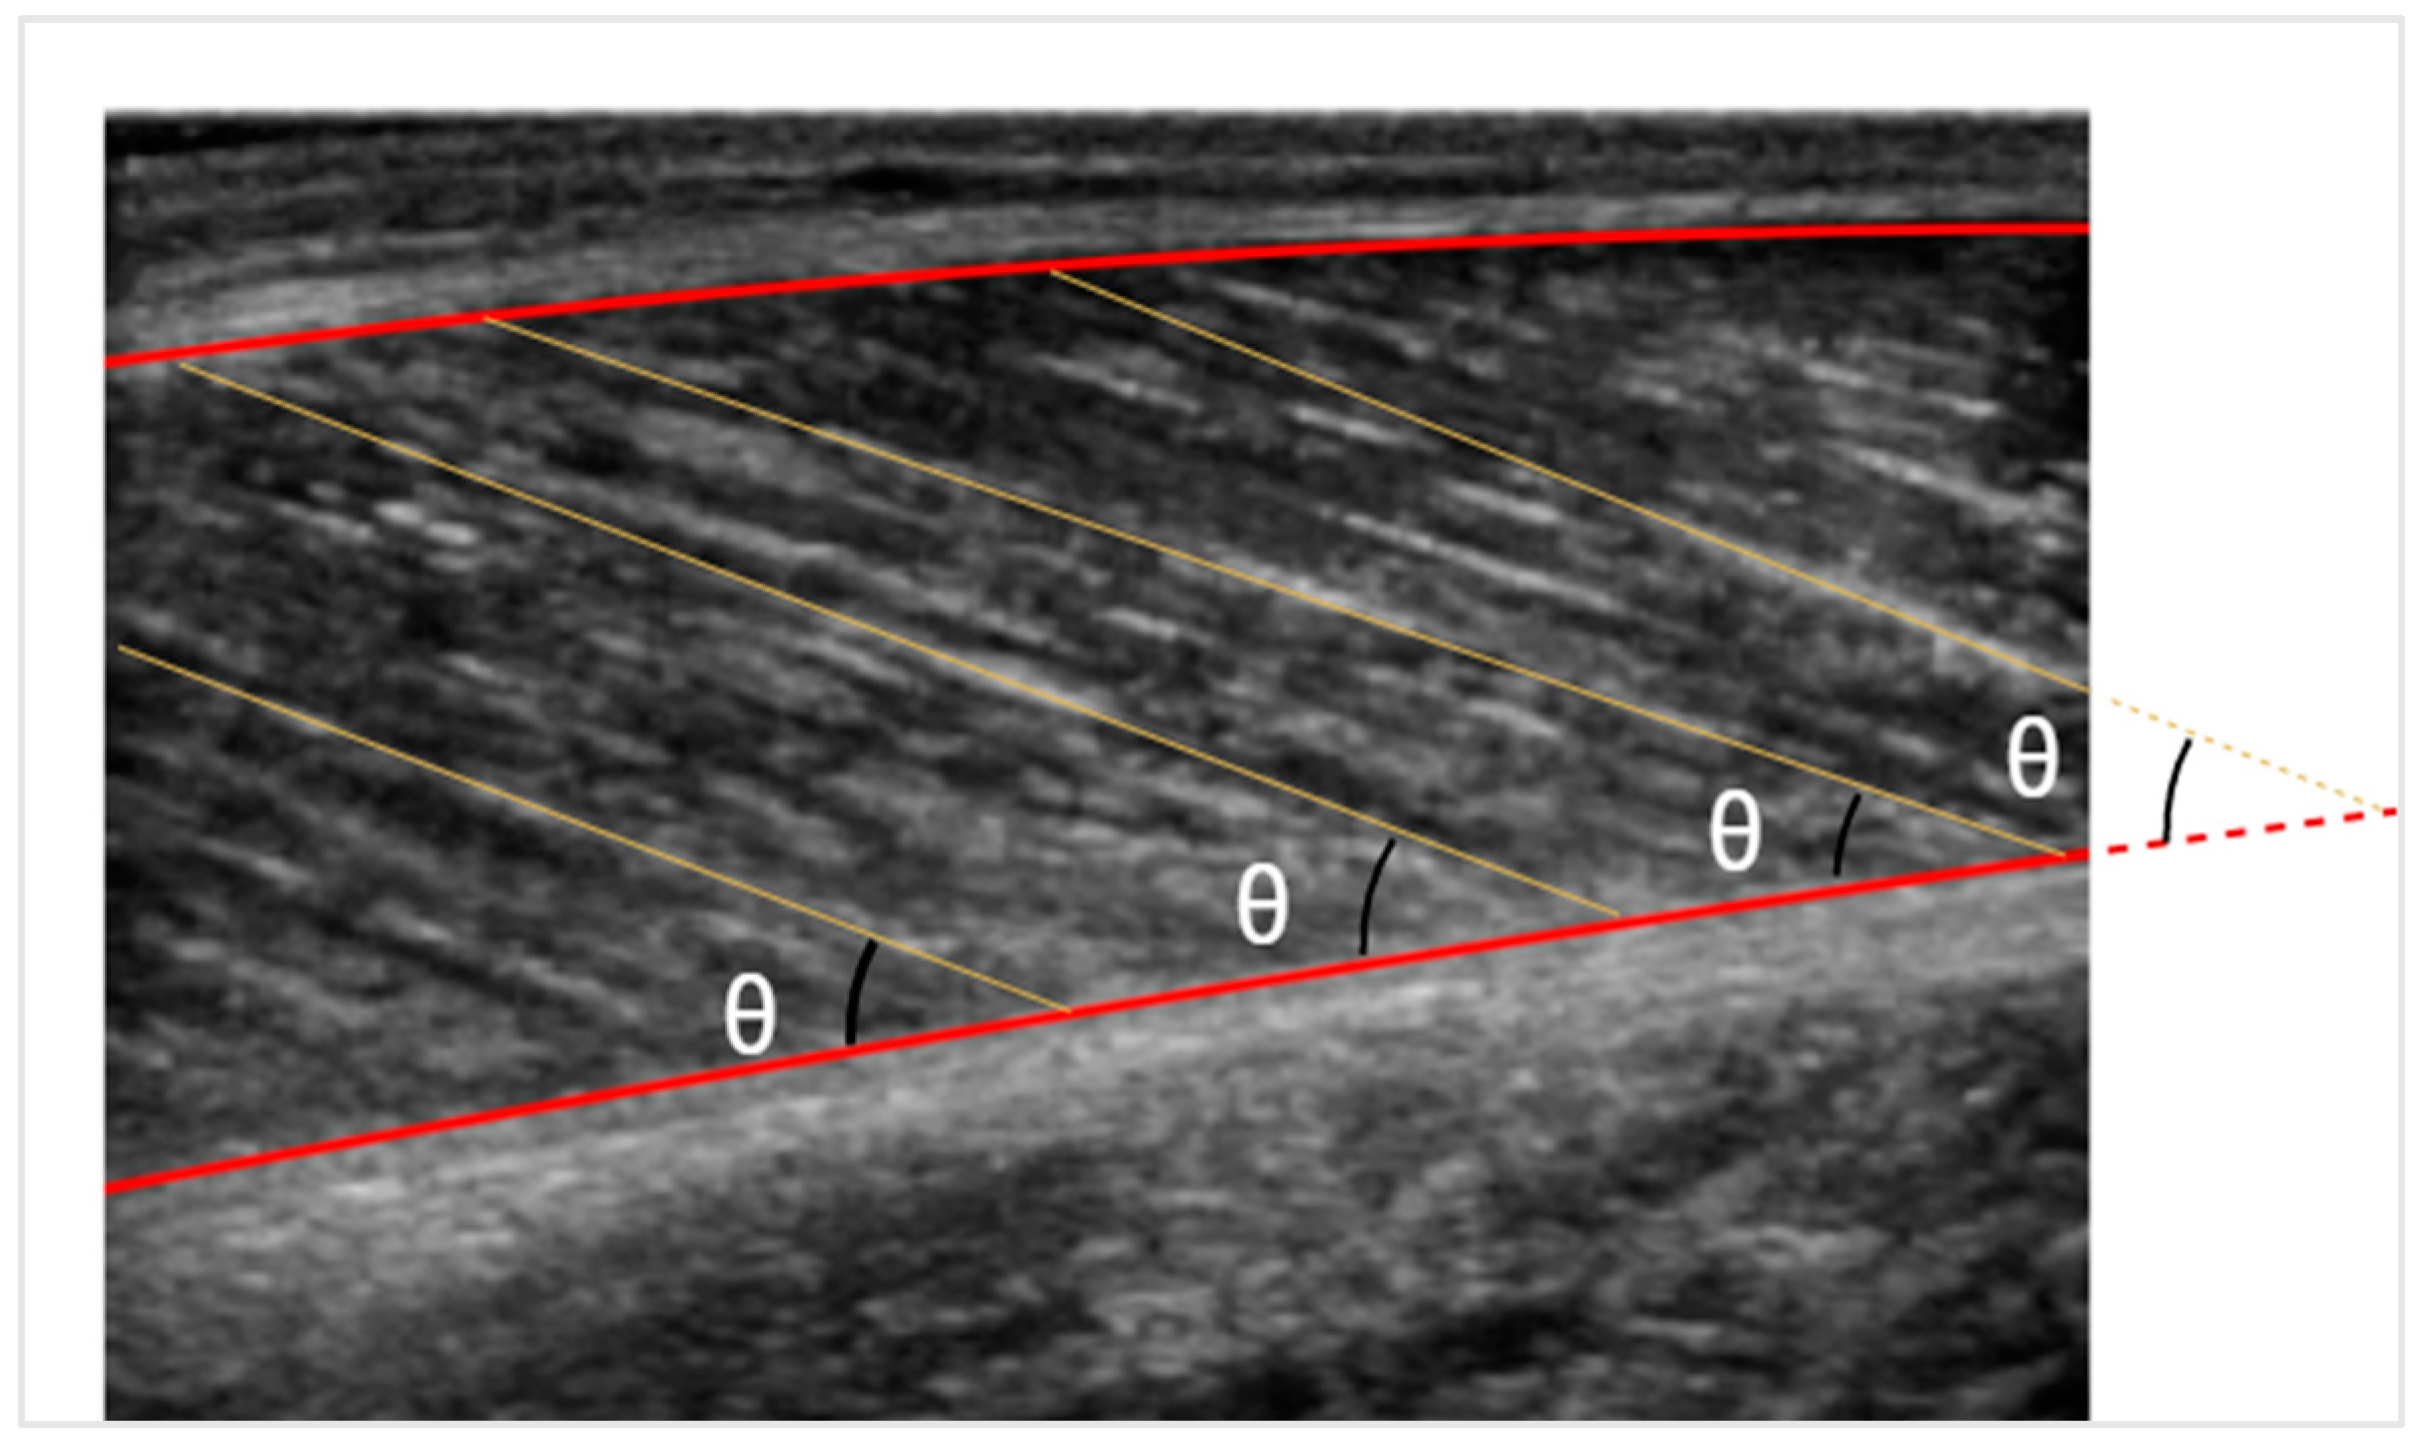

2.3.2. Pennation Angle & Fascicles Length Measurements